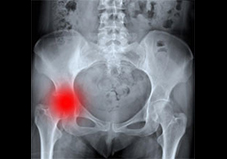

یک مطالعه جدید نشان داده است که میتوان از هورمون رشد برای درمان پوکی استخوان در زنان مسن با موفقیت استفاده کرد و تاثیر این درمان برای سالها در اسنخوان های این زنان باقی میماند. استئوپروز یا پوکی استخوان مهمترین علت شکستگی در استخوان های لگن در سنین بالا و بخصوص در خانم ها است. خانم ها در سنین بالا سه برابر مردان دچار پوکی استخوان و شکستگی های ناشی از آن میشوند.

نتایج مطالعه نشان داد که در زنانی که هورمون رشد دریافت کرده بودند نه تنها استحکام استخوان ها بیشتر بود بلکه احتمال شکستگی در ده سال مطالعه، نصف آنهایی بود که برای آنها از این هورمون استفاده نشده بود. نتایج این مطالعه در مجله The Journal of Clinical Endocrinology & Metabolism منتشر شده است.